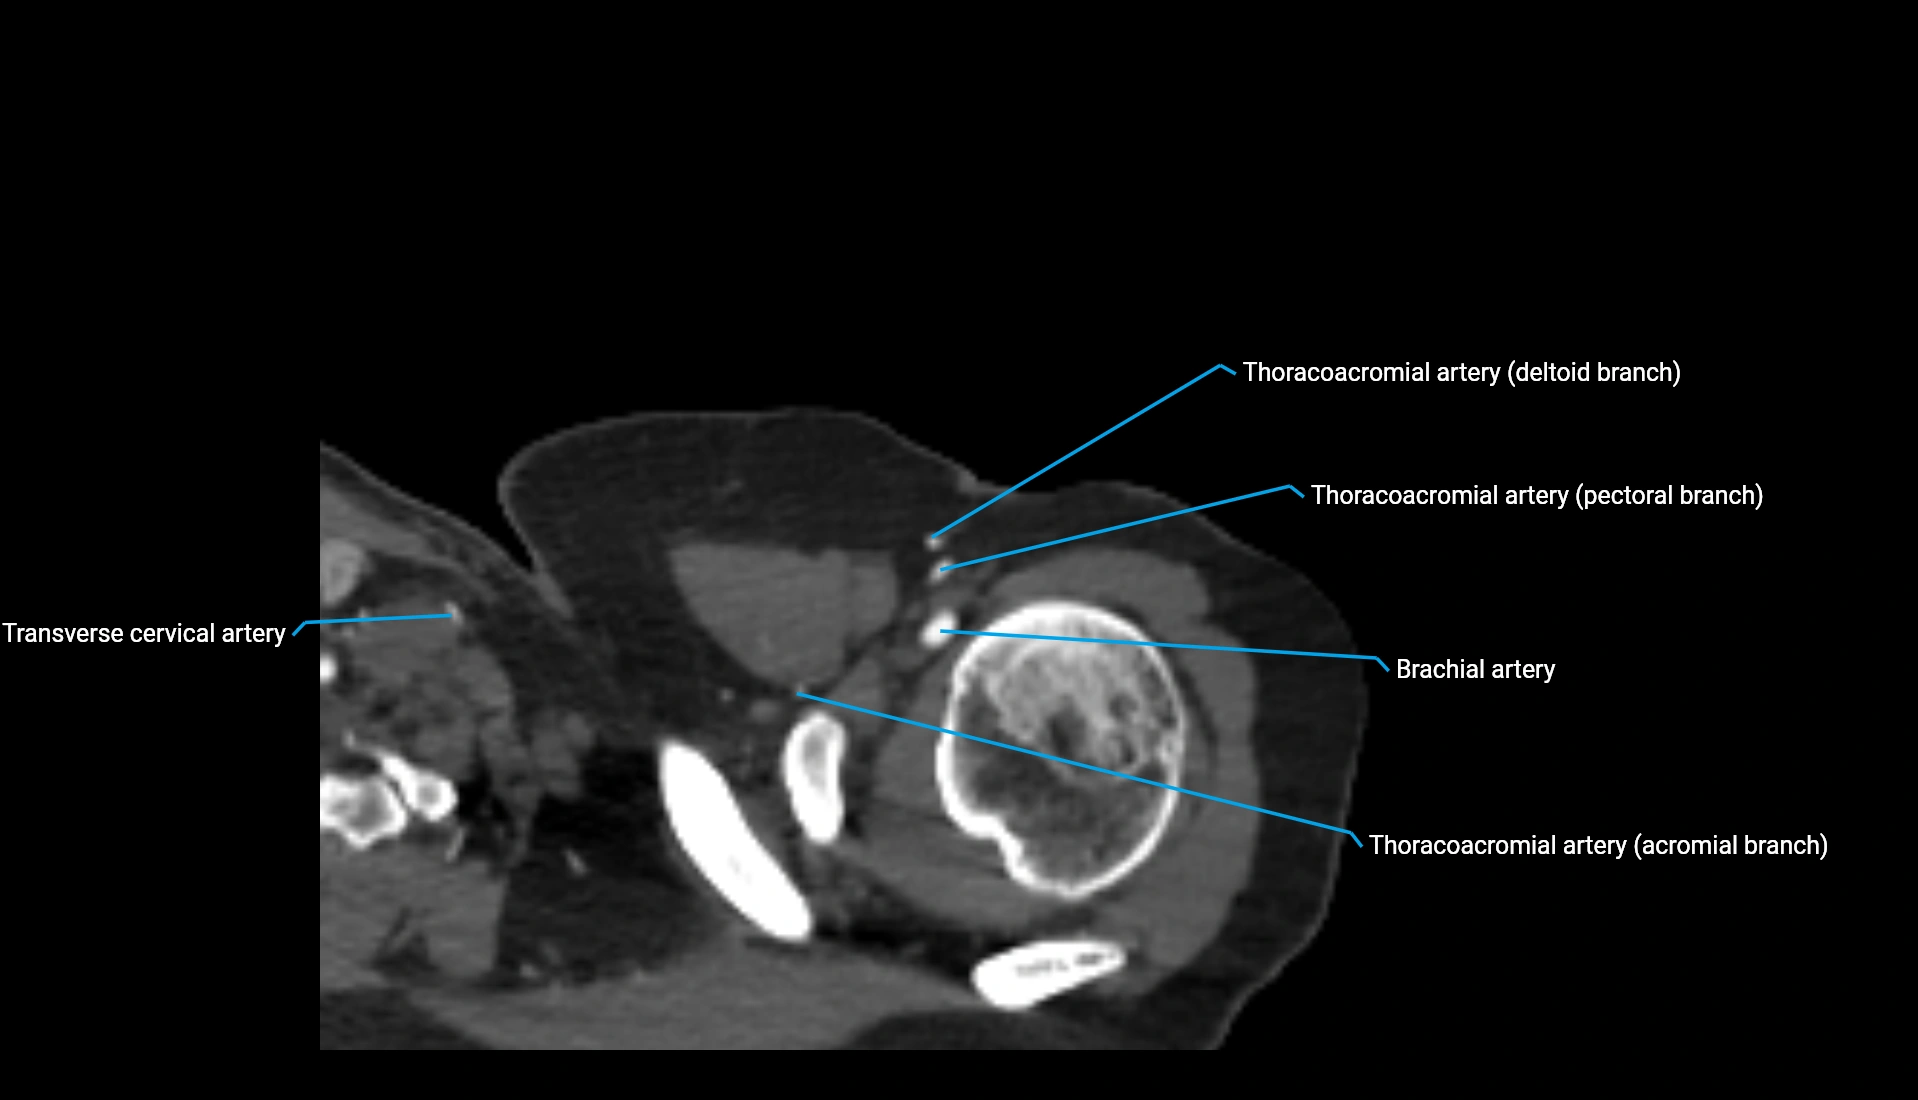

CT Appearance

Non-Contrast CT:

• Cortex: High-density, sharply defined

• Subchondral bone: Dense cancellous matrix

• Articular surface: Smooth concave contour articulating with the capitellum

• Excellent for evaluating bone integrity, alignment, and subtle fractures

Post-Contrast CT:

• Bone: No enhancement

• Joint capsule and synovium: Mild enhancement outlining the joint

• Improves contrast between soft tissues and bony margins

• Useful in detecting subtle joint abnormalities or postoperative changes